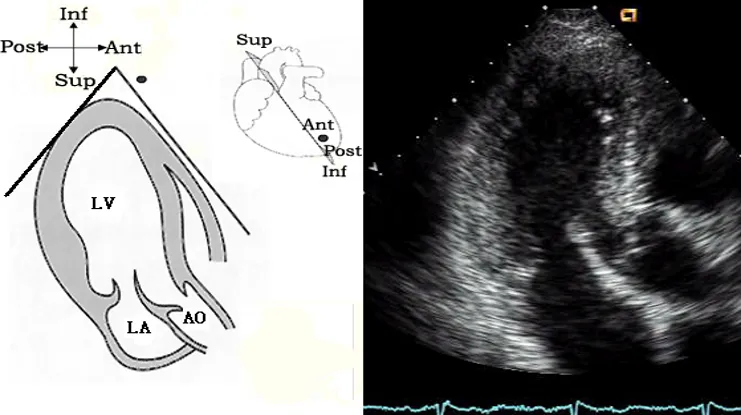

胸骨旁左室长轴切面

探头位置:探头置于胸骨左缘3、4肋间,检查声束平面与右锁骨关节和左乳头连线平行。

观察内容:

● 腔室大小:右室,左房,左室,主动脉根部及升主 动脉近端。

● 室壁厚度:前室间隔和左室后壁。

● 瓣膜活动:二尖瓣,主动脉瓣(右冠状动脉瓣和无冠状动脉瓣)。

● 室壁运动: (前室间隔和左室后壁)。

● 心功能测定